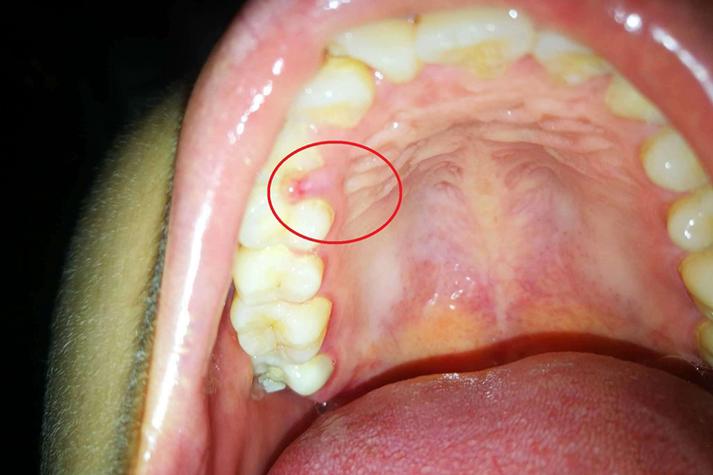

- 上颚能看到白色、红色斑块或溃疡,且长时间不愈合。

- 感觉上颚有固定的肿块或凸起。